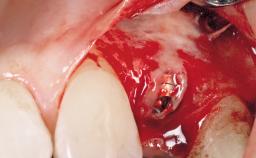

Late Placement of an Implant in a Maxillary Left Central Incisor Site

Type of Implants Two-Piece

Attachment Two-Piece

Bone Augmentation Horizontal|Staged

Augmentation Materials Xenogenous|Membrane